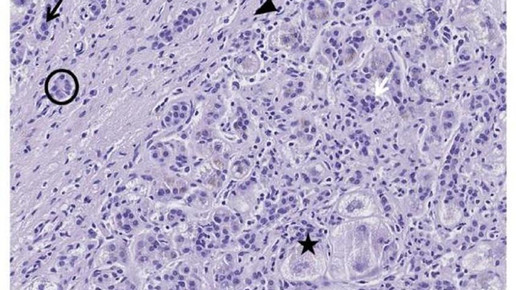

Weitere Analysen ergaben, dass die Verbesserung auf einen starken Rückgang der Kupfermengen zurück zu führen war. Speziell die als Mitochondrien bekannten „Kraftwerke der Zellen“ profitierten stark von der sinkenden Kupferlast und konnten ihre Funktion wieder voll aufnehmen. Methanobactin verhinderte ein Absterben von Leberzellen und beugte einem Leberversagen vor.

Bei der Kupferspeicherkrankheit ist der Körper nicht mehr in der Lage, überschüssiges Kupfer aus der Nahrung über die Galle in den Darm auszuscheiden. Stattdessen lagert Kupfer sich in der Leber und anderen Organen ab und kann dort schwerste Schäden verursachen.

Im Gegensatz zu der herkömmlichen Therapie konnte Methanobactin auch in Stadien schwerer Schädigung innerhalb weniger Tage die Kupferüberlastung der Leberzellen beseitigen und ein Organversagen verhindern. Zudem war der Wirkstoff im Modell sehr gut verträglich.